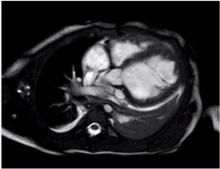

This video shows a female toddler with diagnosed idiopathic dilated cardiomyopathy. The patient presented with worsening symptoms of congestive heart failure, and was admitted to the critical care unit for observation and optimization of medical therapy. During the hospitalization, an echocardiogram was performed, and demonstrated severely depressed biventricular cardiac function, with ejection fraction less than 10%. While admitted, the patient began to demonstrate signs of multi-organ failure and troubling dysrhythmias. The patient was listed for cardiac transplantation as a Status 1A, and evaluated for mechanical circulatory support. The patient was temporized with a Berlin Heart Excor® left ventricular assist device, and subsequently organ function improved. After a few weeks, surveillance echocardiograms began to demonstrate a trend towards improving myocardial function. A multi-disciplinary group initiated the discussion of transitioning the child’s recovery strategy away from transplantation.